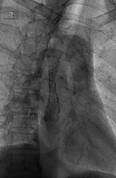

据61岁的王先生自诉,他进行性吞咽困难已经长达3个月时间 ,通过市中心医院确诊为食道癌。放射科主任余开湖博士为王先生采用碘125粒子支架治疗食管癌,使食管通畅,并在腔内用碘125粒子放射治疗食管癌。目前患者康复出院。

据余主任介绍,所谓碘125粒子支架治疗方法,就是用支架撑开接近堵塞的食道,让患者能正常进食,确保患者身体营养需要的同时,采用放射性碘125粒子植入术,其方法是通过影像学导引技术(超声、CT、MRI)将放射性核素直接植入肿瘤靶体积内或肿瘤周围(腔内),通过放射性核素持续释放射线对肿瘤进行杀伤,达到治疗肿瘤的目的。由于放射性粒子只对局部持续作用,因此对肝肾及全身脏器功能影响较少,不良反应较轻。近距离腔内照射主要应用于食道癌、胆管癌。